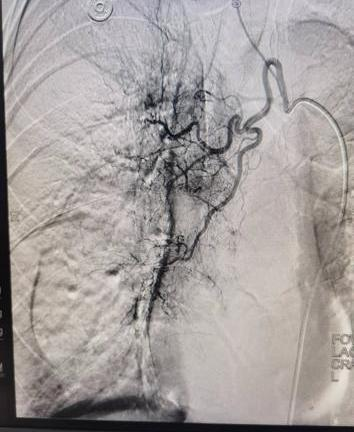

案例一:谭先生,66岁,右肺鳞癌IIIA期。2025年11月18日,在DSA引导及局麻下行经导管支气管动脉栓塞化疗术,术后肿瘤血供明显减少。

栓塞前血供丰富                                                 栓塞后血供明显减少